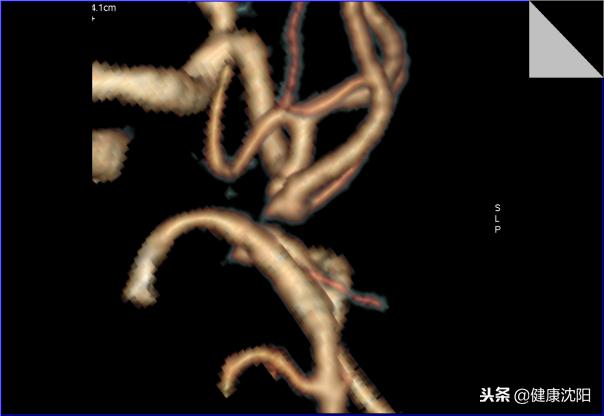

简单地说就是将不在同一片面的组织或血管重组到一个平面上显示的技术。它能显示血管壁、血管腔内的病变,可以判断有无斑块,斑块的性质,血管与周围组织的关系等等,当VR、MIP发现管腔狭窄或扩张时,可以通过CPR明显病因。探针技术是在CPR拉直血管的基础上,探测感兴趣区域的血管内壁情况的技术。

abc:冠脉CPR曲面图像、拉直图像及相应病变血管截面的探针图像